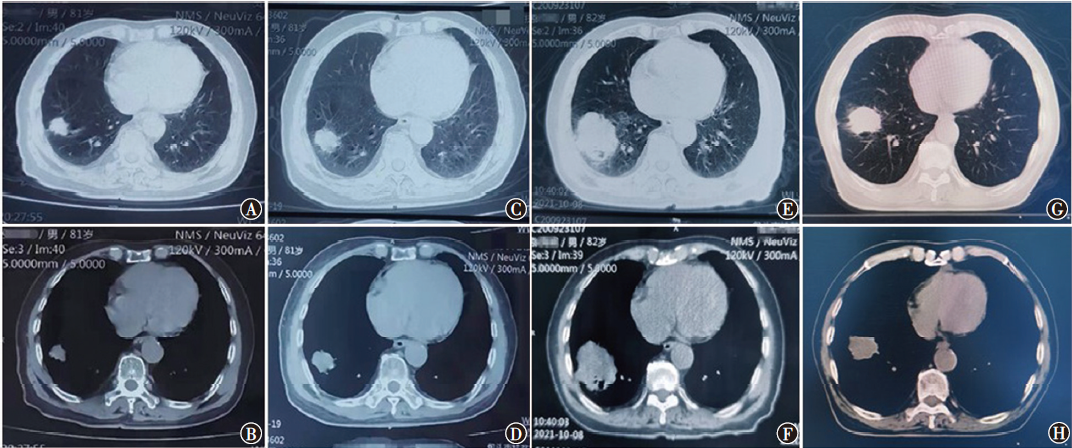

在非小细胞肺癌(NSCLC)的诸多驱动基因中,转染重排(RET)融合基因是一种新型突变基因,存在于1%~2%的NSCLC患者中。普拉替尼是一种RET抑制剂,用于靶向治疗RET融合阳性的NSCLC成人患者。现报道包头市中心医院收治的1例RET融合阳性NSCLC小肠转移老年患者的诊断过程、治疗方案及出现的不良反应,供临床参考。